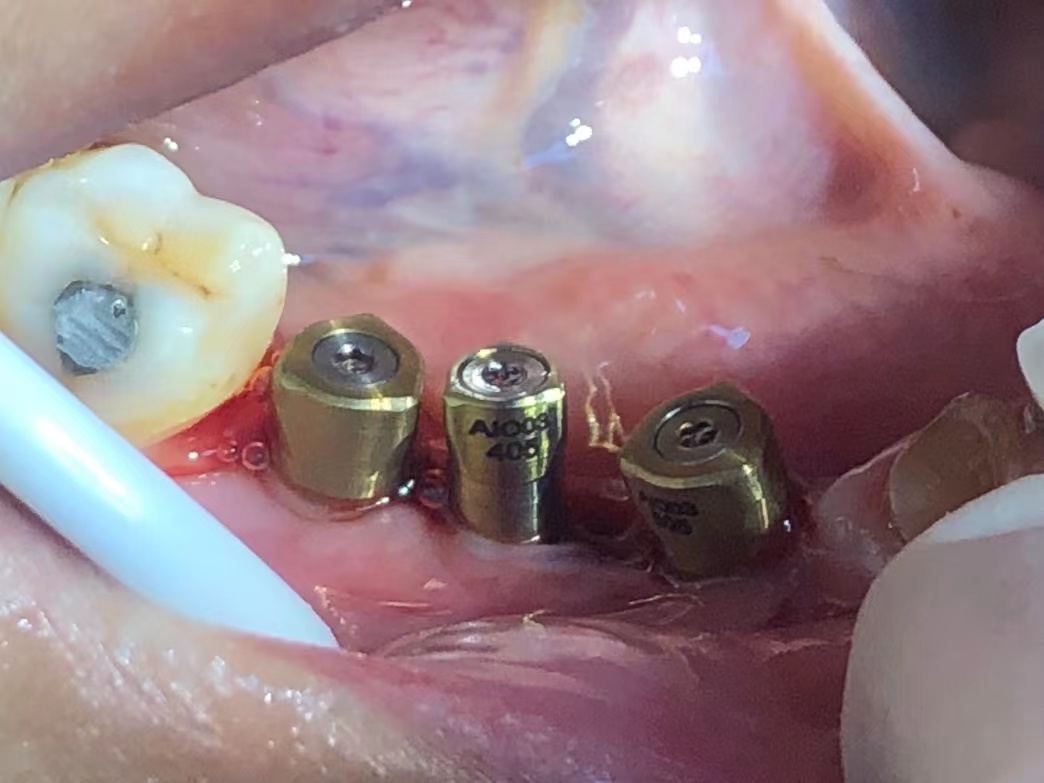

病例展示7

3合一數字化愈合基台         减少就诊次数、降低配件成本、降低戴牙时间、可以口扫、藻酸盐、硅橡胶取模方式!